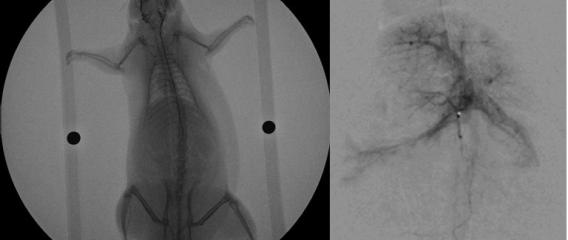

Nanoparticle Delivery to Brain comparison